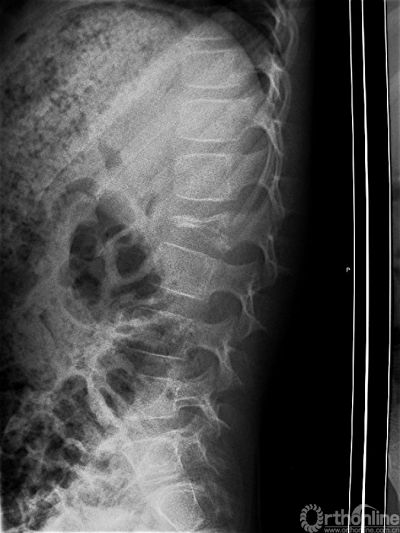

图1 男性,7岁,腰部疼痛,术前腰椎侧位片,L2椎体嗜酸性肉芽肿病变,椎体严重压缩变形。